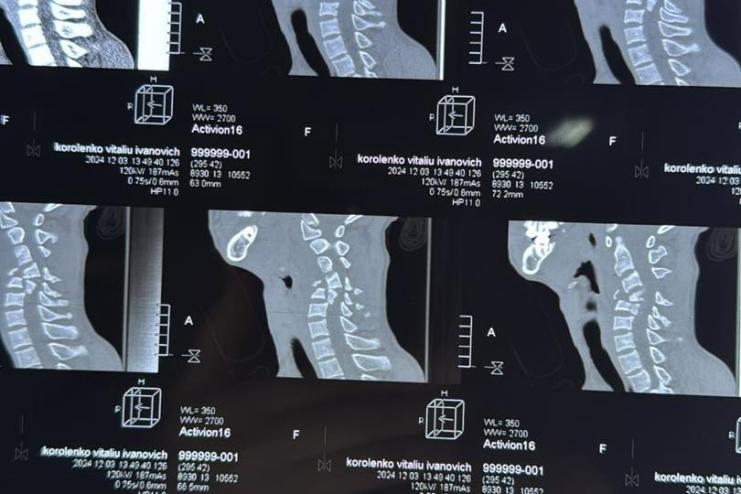

За інформацією медиків, хлопець допомагав тату лагодити покрівлю і внаслідок падінняхлопець зазнав таких ушкоджень:

🔹 закрита ускладнена вертебральна травма;

🔸 забій шийного відділу спинного мозку важкого ступеня;

🔹 переломовивих тіла шийного хребця С4, уламковий перелом тіла С5, перелом тіла С6.

4 грудня 2024 року командою нейрохірургів була проведена складна високотехнологічна операція, яка включала:

🔹 корпоректомію шийного хребця С4;

🔸 дискектомію С3-С4, С4-С5;

🔹 передній спондилодез із використанням міжтілової телескопічної титанової опори на рівні С3–С5.